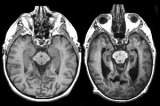

Aproximadamente 46.8 millones de personas viven con el padecimiento en el mundo.

Aproximadamente 46.8 millones de personas viven con el padecimiento en el mundo. Crédito: iStock